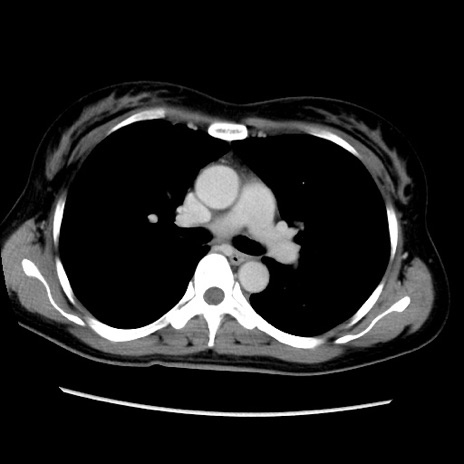

症例39(横断像)

【症例】40歳代女性

【主訴】上下腹部痛

【現病歴】2日目から下腹部痛あり。夜間は痛みで眠れなかった。昨日より上腹部痛と下痢が出現。臥位で痛みは軽快したため、休んでいた。本日になって臥位でも立位でも痛みが強くなってきたため救急要請。

【既往歴】子宮内膜症

【身体所見】部:平坦・軟、左上下腹部に圧痛あり、反跳痛あり。

【データ】WBC 21800、CRP 26.78